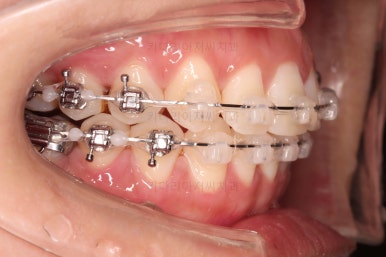

이제 미니스크류가 등장합니다.

상하좌우 발치 공간의 크기와 위치가 제각각이라서 당겨지는 양과 속도가 차이납니다.

그래서 미니스크류를 반드시 써줘야 합니다.

윗니도 발치를 했고요.

발치공간을 서서히 줄여 나갑니다.

입매 변화도 신중하게 체크합니다.

윗니는 어느 정도 틈이 많이 줄었는데요. 아랫니는 기약이 없죠.